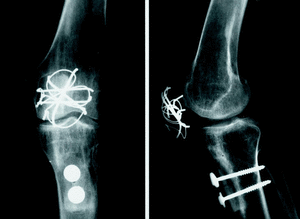

Ante la situación funcional, se indicó un aloinjerto de tendón rotuliano. En el acto quirúrgico se realizó un abordaje medial iterativo, evitando la cara lateral de la rodilla por donde pasaba y se palpaba la anastomosis vascular del colgajo muscular del dorsal ancho. La incisión se continuó directamente al periostio para evitar desvascularizar medialmente la piel y se disecó por debajo de la plastia del dorsal ancho desplazándola lateralmente. Se localizó el borde distal de la rótula, se cruentó y preparó un lecho para el injerto, liberando el fondo de saco subcuadricipital de adherencias. En la rótula la fijación del aloinjerto se realizó mediante un cerclaje tipo obenque en sentido horizontal y vertical. Distalmente con sierra oscilante se preparó un lecho de unos 3 cm de largo y 1 cm de ancho y profundidad en el que se colocó el extremo distal del aloinjerto criopreservado de tendón rotuliano, procurando darle la tensión adecuada en extensión mediante su desplazamiento distal, de tal forma que el extremo inferior de la rótula se situara a un través de dedo por encima de la interlinea articular y realizando la osteosíntesis con 2 tornillos maleolares con arandela (figs. 1 y 2). Una vez completada la fijación, se comprobó que se podía realizar una flexión de 100° sin tensión excesiva del injerto. Se realizó un cierre por planos con drenaje aspirativo e inmovilización de rodilla en extensión.

Figura 1. Aspecto peroperatorio de perfil del aloinjerto de tendón rotuliano implantado para reconstruir el aparato extensor. Se puede apreciar la fijación proximal en la rótula mediante obenque alámbrico horizontal y vertical y la fijación distal tibial con 2 tornillos maleolares con arandela.

Figura 2. Aspecto peroperatorio de frente del aloinjerto de tendón rotuliano. El colgajo de dorsal ancho ha sido rechazado lateralmente.

Al año de seguimiento, en las radiografías se observó la incorporación progresiva del extremo óseo del injerto (fig. 3). La paciente camina sin ortesis y sin bastones, existiendo atrofia del cuádriceps y un balance articular activo de 0-120° (fig. 4); el injerto de tendón rotuliano se puede palpar subcutáneamente, al igual que las agujas de Kirshner del obenque rotuliano.

Figura 3. Rx AP y lateral del aloinjerto de tendón rotuliano al año de la intervención.